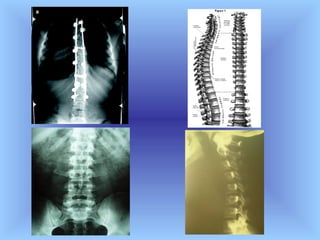

Anatomía de la columna vertebral

Anatomía y patologías de espalda Estructura ósea de la espalda . La parte central de la espalda es la columna vertebral, especialmente la zona que va desde la parte superior de las vértebras torácicas hasta el interior de las vértebras lumbares que contienen la médula espinal y que generalmente tiene una curvatura que da forma a la parte posterior. El costillar se extiende desde la espina dorsal hasta la parte superior de la espalda, más de la mitad de la espalda deja un área sin protección entre el interior de las costillas y las caderas. La anchura de la parte posterior de la espalda está definida por los omóplatos, los huesos amplios y planos de los hombros.

Anatomía de lacolumna vertebral

Anatomía y patologíasde espalda Estructura ósea de la espalda . La parte central de la espalda es la columna vertebral, especialmente la zona que va desde la parte superior de las vértebras torácicas hasta el interior de las vértebras lumbares que contienen la médula espinal y que generalmente tiene una curvatura que da forma a la parte posterior. El costillar se extiende desde la espina dorsal hasta la parte superior de la espalda, más de la mitad de la espalda deja un área sin protección entre el interior de las costillas y las caderas. La anchura de la parte posterior de la espalda está definida por los omóplatos, los huesos amplios y planos de los hombros.